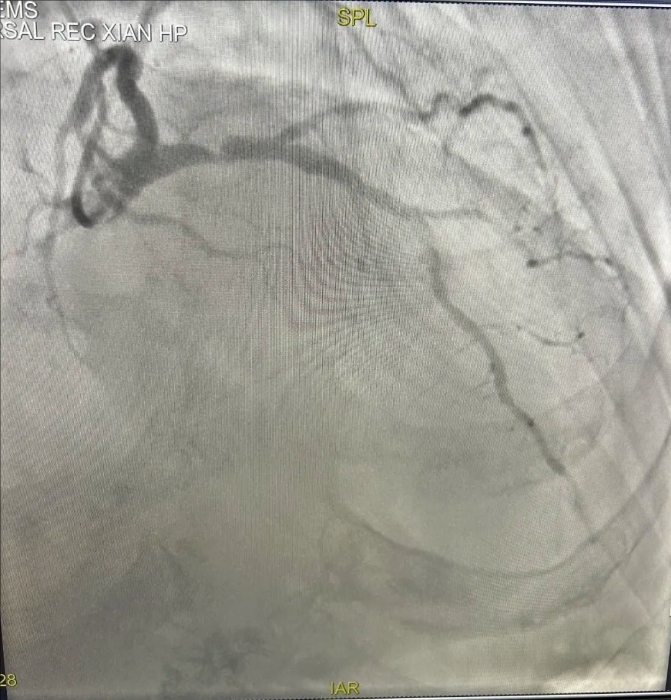

患者71歲,男性,合并長期糖尿病、腎病、高血壓病史,近1周反復(fù)出現(xiàn)活動后胸悶、氣短。入院后,行冠脈造影提示,前降支近段嚴(yán)重狹窄,且存在嚴(yán)重鈣化。血管內(nèi)超聲(IVUS)顯示前降支近中段彌漫性鈣化,近段270°環(huán)形鈣化,像“石頭”一樣硬,給介入治療帶來了很大難度。

支架前,LAD6段狹窄